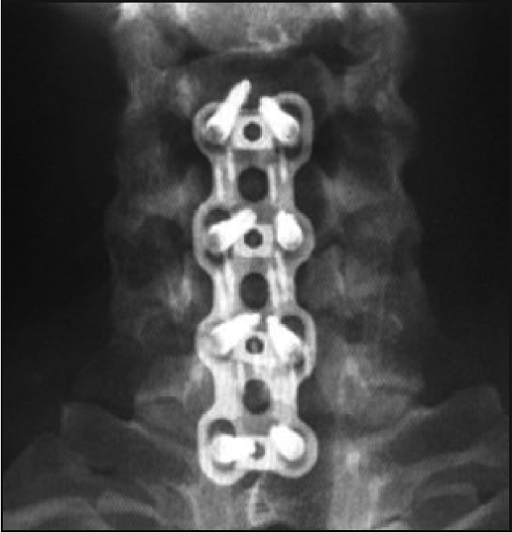

Clinical Cases

“as·C·p” plate with corpectomy prosthesis

Implanted: intervertebral disc C Disc PEEK together with the bone substitute Cerasorb M – granules, supported with cervical plate asCp L = 65mm with eight locked in plate cerival screws